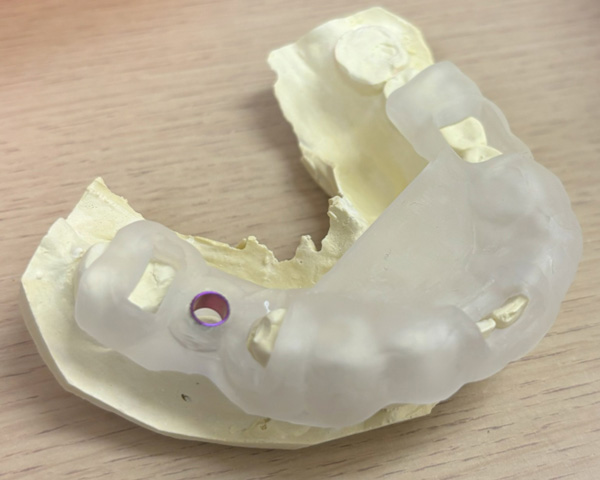

インプラント手術を行いました。

手術の時に使用するサージカルステント